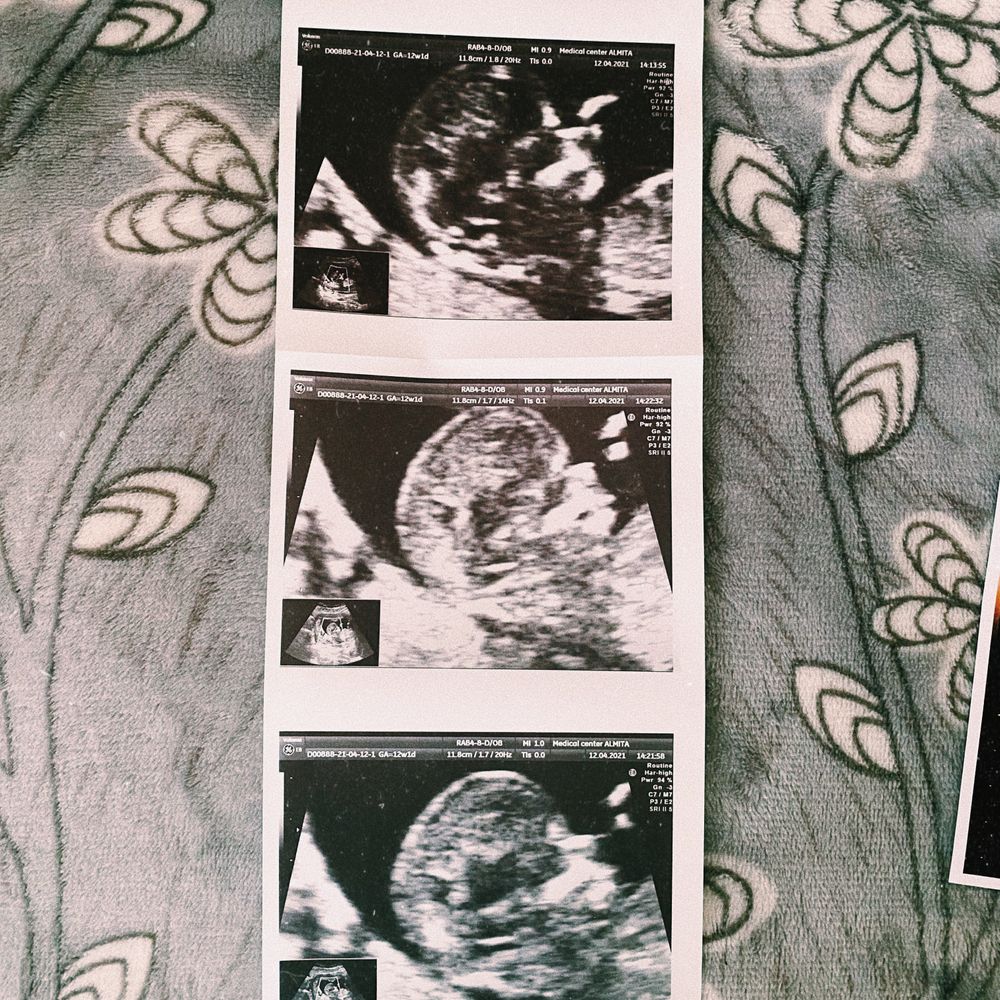

Когда-то я читала такие посты у девочек и думала что напишу свой🙂 после двух замерших в 2020, здоровая беременность была для меня чем-то не достижимым. Но вот она❤️ Ттт все проходит отлично, да был токсикоз, есть прыщи, изжога по вечерам, но это все такие мелочи по сравнению с тем что в тебе растёт чудо 🐣 через неделю будем подтверждать пол, но по первому скринингу 95%, что у нас будет сынок🤱🏽Блин от одной мысли что осенью стану мамой я плачу, и от мысли о моем малыше , так хочется чтоб он был здоровым🙏🏼 Меня спасает доплер, с 11 недель слушаю сердечко, поэтому на узи теперь не бегаю как в начале, а до первого скрининга я была там 4 раза😁 жду шевелений с нетерпением☺️ Фото со скрининга😊